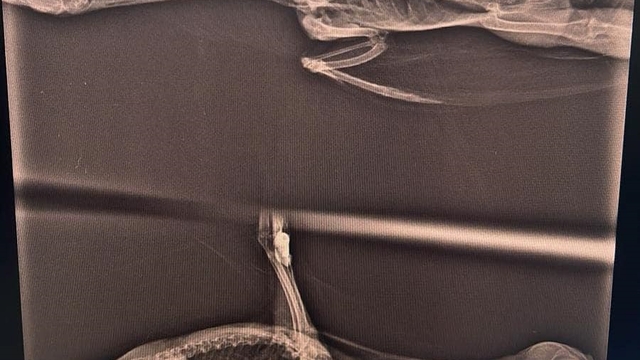

Düzce Doğa Koruma ve Milli Parklar Şube Müdürlüğü ekipleri, Efteni Gölü çevresinde yaptıkları denetimlerde boğazına misina iğnesi takılan saz tavuğunu tespit etti. Şube müdürlüğünde görevli veteriner hekimlerinin muayenesinde saz tavuğunun yutak bölgesine takılan misina iğnesi, başarılı bir operasyonla çıkarıldı. Tedavisi tamamlanan ve sağlığına kavuşan saz tavuğu yavrularının olduğu bölgeye bırakıldı.